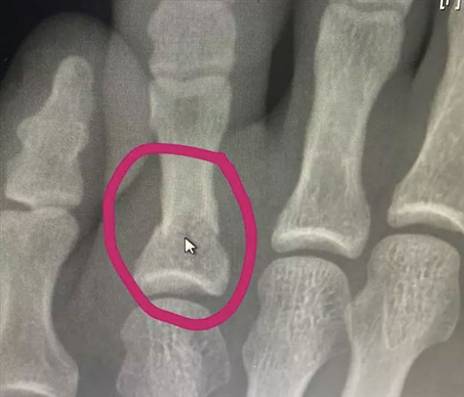

צילום הרנטגן שמראה: חאביב שבר את הרגל

שנה גודל פונט א א א א

צילום הרנטגן של חאביב